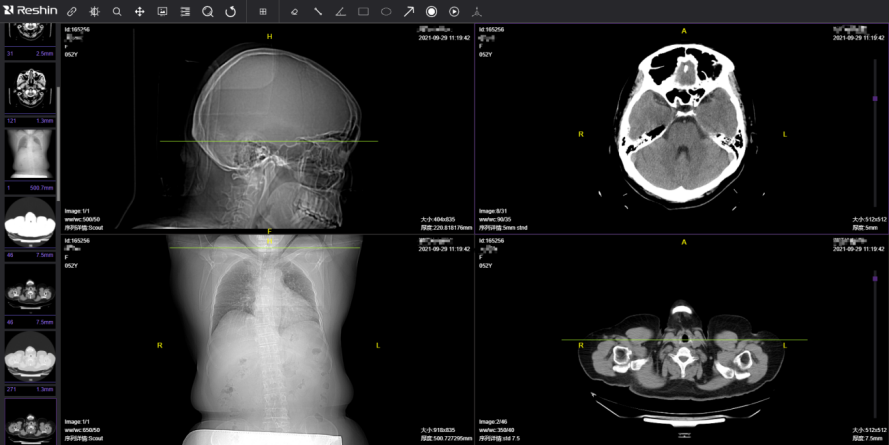

放射影像軟件——支持影像數據的接收、瀏覽;影像放射后處理及分析;三維后處理。

(支持影像數據的接收、瀏覽)

(影像放射后處理及分析)

(三維后處理)